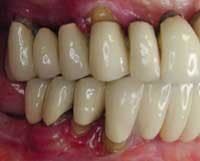

Photos of same woman before treatment

The case above is an excellent example in which someone who experiences continued periodontal breakdown around teeth despite treatment will fare better with implants and resist problems with future decay. Dr. Andrew Alpert of Aventura, Fla., placed the implants.

To help a patient understand the benefits of implant restoration, show before and after images of another patient and talk about the stability and improved esthetics achieved.